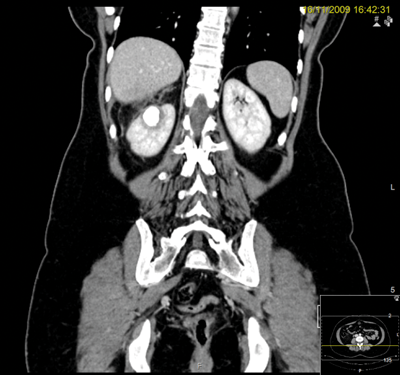

A 44-year-old woman presented with several months of malaise and right flank pain. A CT scan demonstrated a 26 x 25mm upper pole calyceal stone with an adjacent abscess that had perforated the capsule and some adjacent atelectasis. She was transferred from a referring hospital and treated with antibiotics and re-imaged.

CT scan.